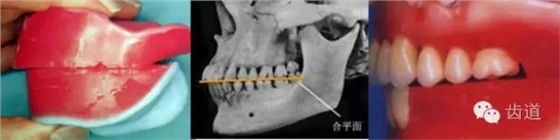

關(guān)于HE平面,有下面這些描述: 1.前端與瞳孔連線平行,于唇下2毫米。平行表現(xiàn)的是水平無傾斜,應(yīng)該是平行于面部的水平線,有可能是瞳孔連線,也有可能是口角連線。唇下2毫米,是年青人的美學(xué)表現(xiàn),對于老人,齊平上唇也許更加美觀,以“f/v”的發(fā)音狀態(tài),確定HE平面的前點更為符合生理學(xué)規(guī)律。 2.上頜最后端,離開翼上頜切跡5毫米。這是一個平均值,有可能在5~7毫米內(nèi)調(diào)整,使得后端平面與鼻翼耳屏線平行。 3.下頜后端,平齊于雙側(cè)磨牙后墊高二分之一。這也是平均值,具體要在患者口內(nèi)做調(diào)整。 4.下頜后端在患者口內(nèi)調(diào)整,使之平齊于舌的外側(cè)緣。過高不利于舌在咀嚼中的輔助運動,過低有可能咬舌。 5.調(diào)整下頜前端平面,使下頜前端略高于下唇上緣,與唇平線平行。 6.HE平面盡量平分頜間距離,與牙槽嵴呈相對平行的狀態(tài)。這是從力學(xué)平衡的原理,對HE平面的要求,能使義齒在使用中更加穩(wěn)定。

借助平面鏟,可以極為便利地形成光滑平整的HE平面。

常見的黃金鏟,后端有5毫米卷邊,按圖示的方法形成上頜平面非常容易。但是卷邊的反面端頭是圓角,所以用在下頜時就不太方便。